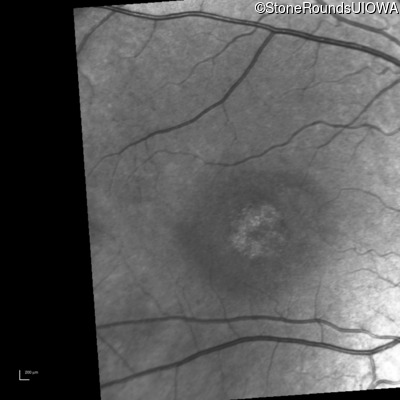

Infrared Fundus Photograph - Right - 10/100 -1

Exemplar

Infrared Fundus Photograph - Left - 10/100 -2